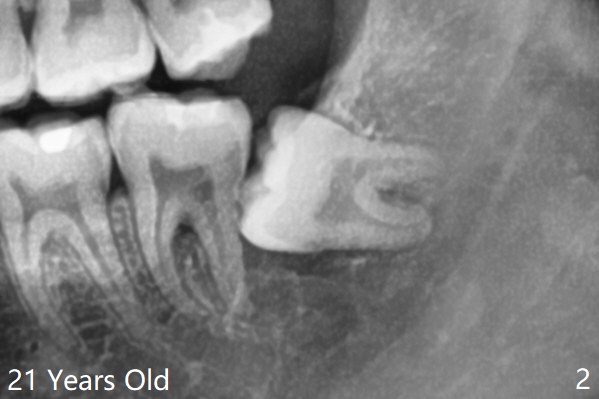

Multiple Sectioning     Last     Next   智齿拔除

Xin Wei, DDS, PhD, MS 1st edition 07/10/2021, last revision 07/18/2021